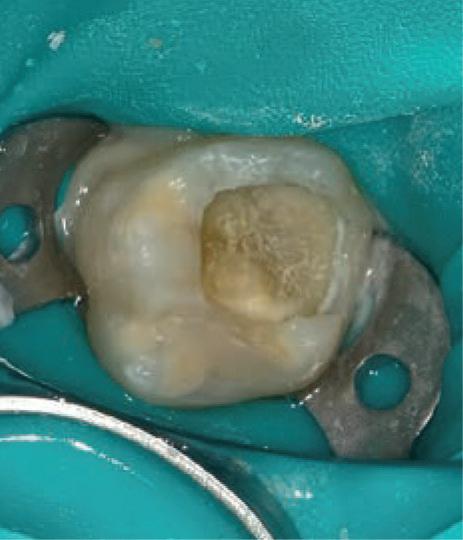

Many of the “valuation” enquiries I received were in fact requests for help with dental business problems in which case the dentist’s hidden agendas were identified and dealt with but valuation not proceeded with. 33 years of examining dental financials, including benchmarking dental practice efficiency, doing tax planning for dentists, helping dentists negotiate practice buy and sell agreements or sensitive dental associateships, gave me a rewarding insight into the Australian dental profession. I was fortunate to enjoy dental client relationships Australia-wide and to observe the differences in practice of financially very successful dentists and some who have struggled.

Knowing your own practice.